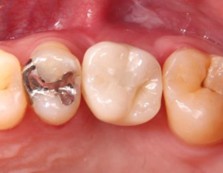

20代 男性

治療前

治療後

治療後- リスク・副作用

(薬・注射・レントゲン・CT・データ分析・骨造成・サージカルステント・血液検査・仮歯) - 年齢/性別

- 20代/男性

- 患者の具体的な症状

- 1年前に左上12 右上1の根の治療をし、その後放置していたら、左上2が破折した。

左上2インプラント補綴 左上1右上1オールセラミック装着。

歯根破折と虫歯による痛み、審美障害を主訴として来院。 - 検査方法

- コーンビームCT、レントゲン撮影

- 診断結果

- 左上2 歯根破折

- 治療詳細

- 左上抜歯後、インプラント埋入1本

骨造成あり 局所麻酔

インプラント治療後、左上1右上1セラミック修復2本 - 通院回数

- 9回

- 治療期間

- 12か月